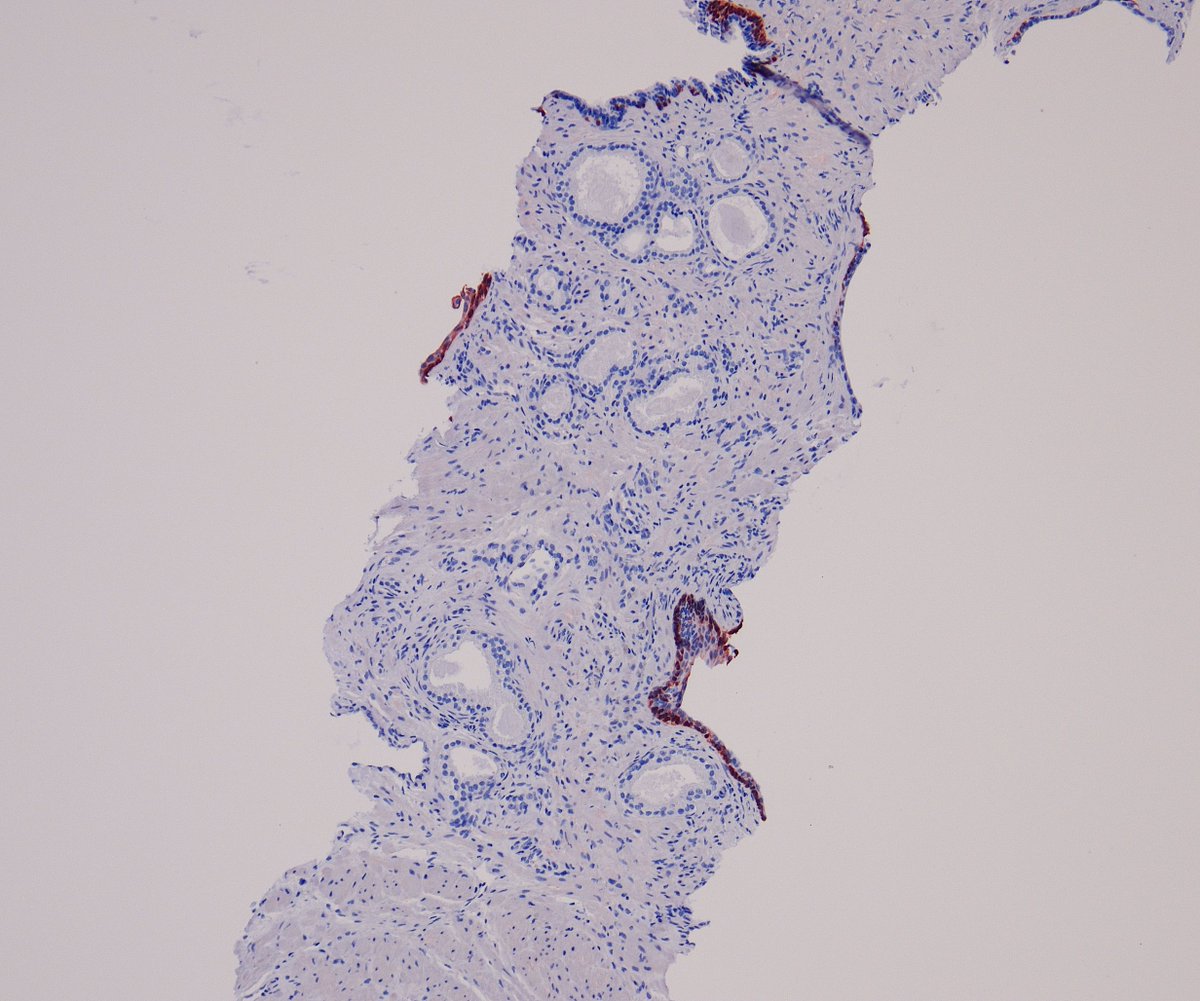

HER2 interpretation is increasingly complex—with evolving definitions come real challenges, especially reproducibility. We’ll cover navigating HER2-low & ultralow in a clinically meaningful way.